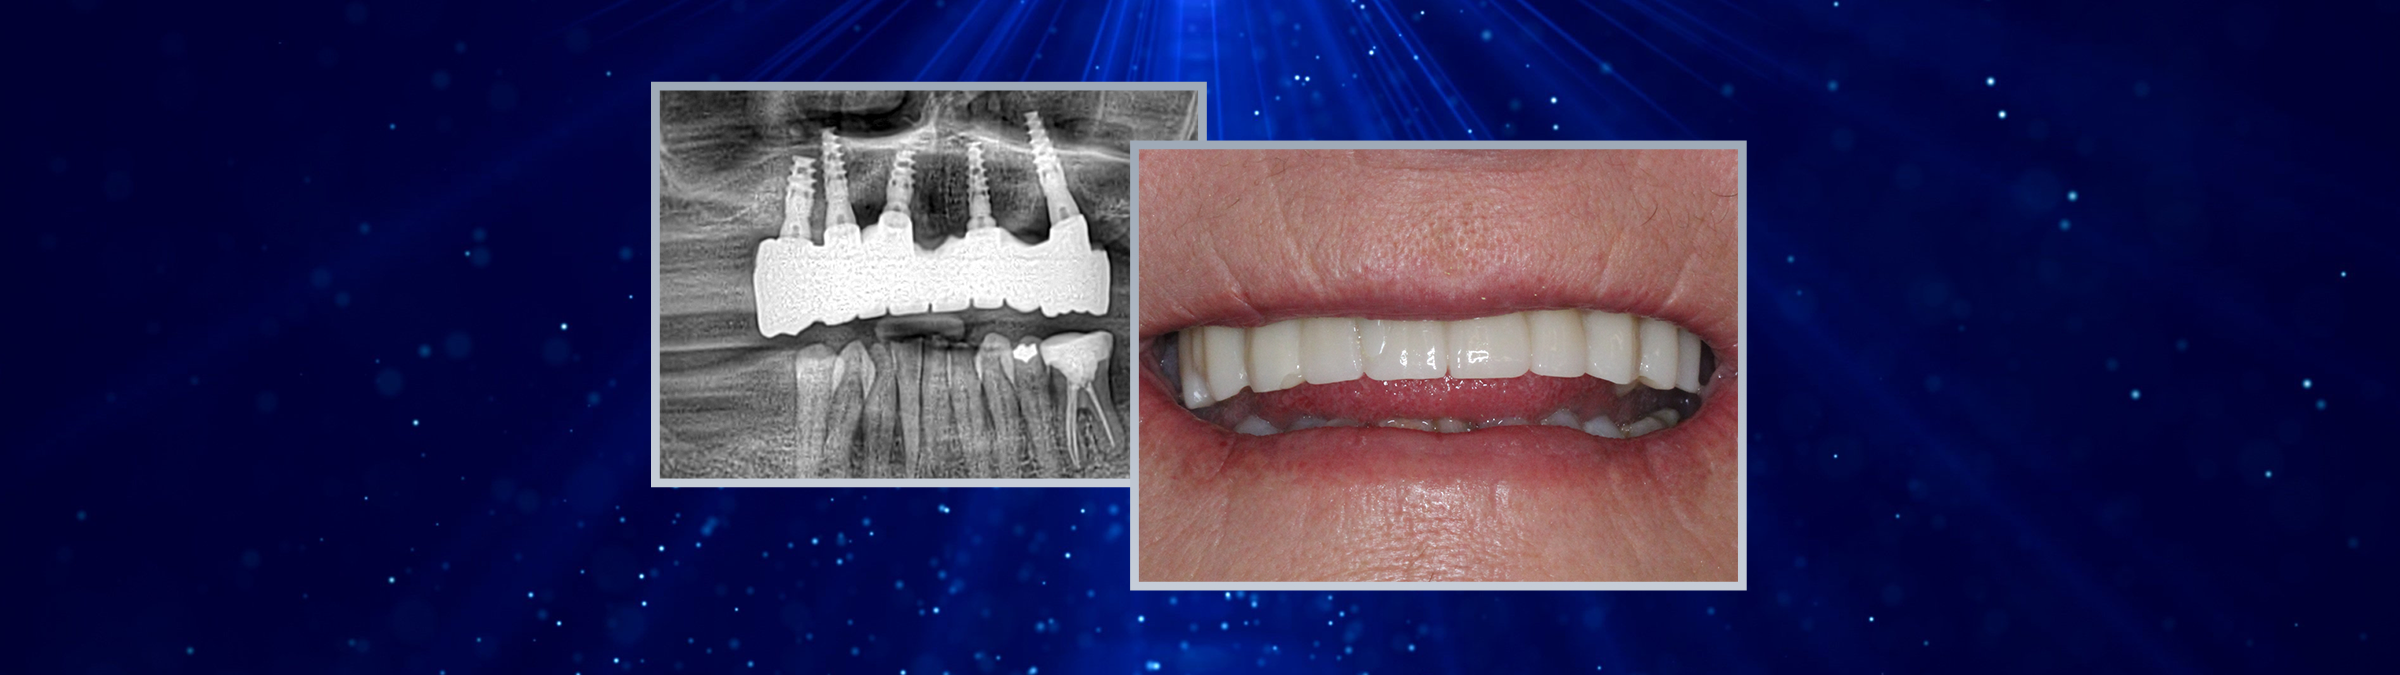

Due to a severely atrophic maxilla, all remaining teeth were extracted under local anesthesia. Immediately following extraction, five DSI conical implants were placed in positions 15, 13, 11, 21, and 24. Cover screws were inserted, and a complete denture was provided as a temporary solution one week post-surgery.

After six months of osseointegration, the cover screws were replaced with DSI multi-unit abutments (MUA) 1.6, and healing caps were inserted. One week after the second-stage surgery, digital impressions were taken at the MUA level using DSI scan bodies and a Dentsply Sirona Primescan intraoral scanner.

Two weeks later, the patient received her FP2 suprastructure, which was mounted using prosthetic screws. The screw access openings were sealed with composite, and custom-made zirconia posts were placed where visible for optimal esthetics.